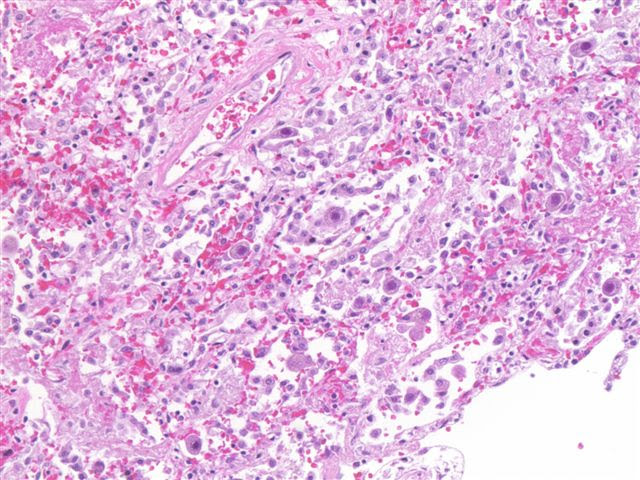

Rhodococcus equi

Recommended to obtain contemporaneous H&E section (AJSP 2007

Nocardia - lung-Fite-Faraco Modified Acid Fast stain #1;